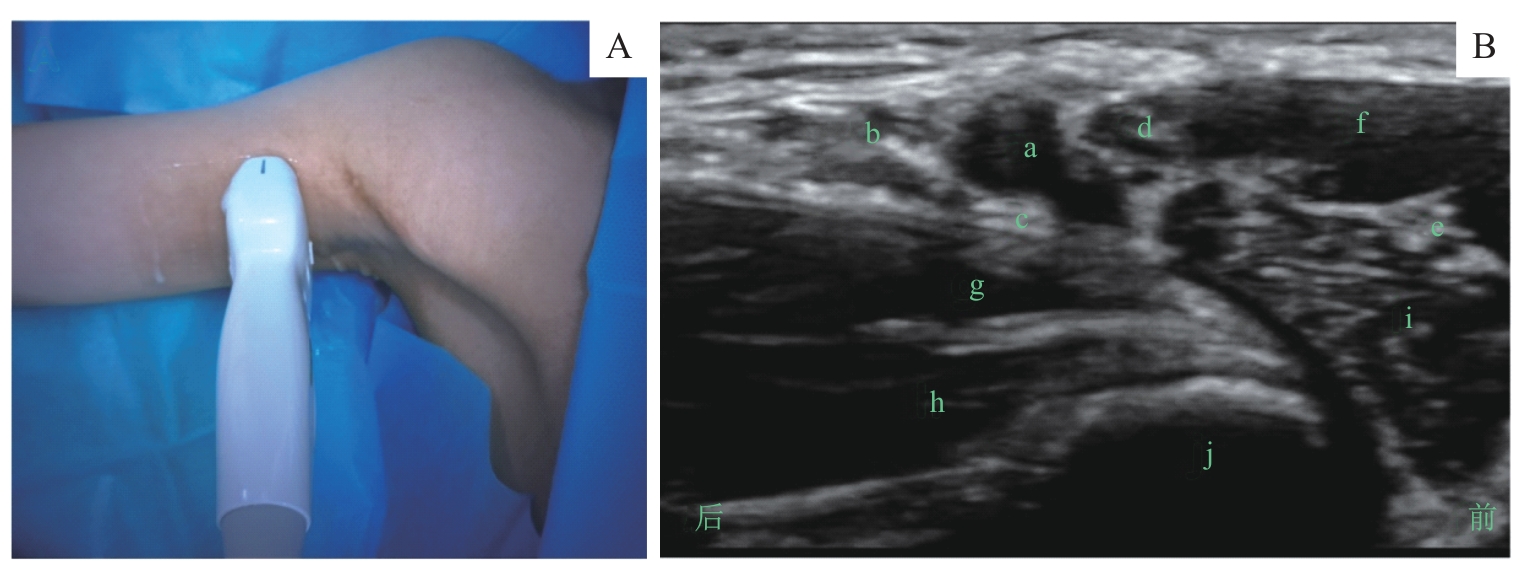

图4 腘窝坐骨神经阻滞的超声定位和影像Note: A. 超声探头体表扫描定位/Surface scanning for ultrasound probe positioning. B. 探头处于图A位置时的腘窝坐骨神经超声影像/Ultrasound image of the sciatic nerve in the popliteal fossa obtained with the probe positioned as shown in figure A. a—坐骨神经/sciatic nerve; b—股二头肌/biceps femoris muscle; c—半腱肌/semitendinosus muscle; d—半膜肌/semimembranosus muscle; e—腘动、静脉/popliteal artery and vein; f—股骨/femur.

Fig 4 Ultrasound positioning and imaging of the sciatic nerve block via the popliteal fossa